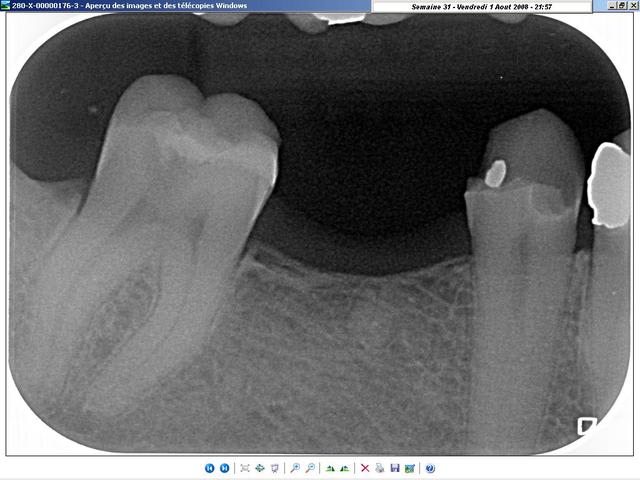

radiologiquement, je ne vois pas trop de différences. A vous de juger.

Les deux cas sont de cette semaine, celui du condenseur, tout frais de cet après-midi; La gutta doit encore être tiède... lol ;-)